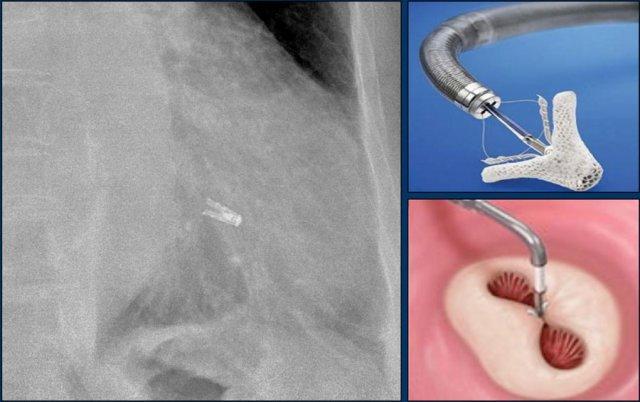

TAVR

TAVR là thay van động mạch chủ qua đường ống thông (transcatheter aortic valve repair).

Van động mạch chủ bị hẹp được sửa chữa bằng cách đặt van nhân tạo vào bên trong van bệnh lý.

TAVR dành cho những bệnh nhân có nguy cơ cao khi thực hiện phẫu thuật mở.

Tỷ lệ thành công của thủ thuật là 90%.

TAVR có liên quan đến tỷ lệ cao hơn về tổn thương mạch máu, hở cạnh van và nhu cầu đặt máy tạo nhịp tim vĩnh viễn.

Van động mạch phổi

Van Melody là van động mạch phổi qua đường ống thông (transcatheter pulmonary valve – TPV).

Đây là tĩnh mạch cảnh bò được khâu vào trong một stent bạch kim-iridi.

Van Melody được đưa vào qua đường ống thông qua da.

Stent Melody này có nhiều vị trí gãy (mũi tên vàng)